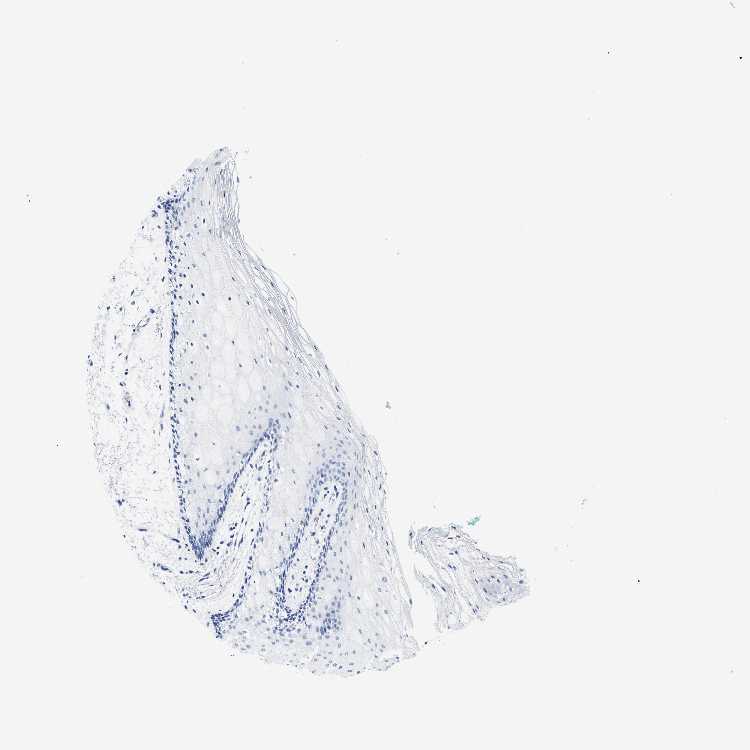

TISSUE PRIMARY DATA ORAL MUCOSA Show tissue menu

ORAL MUCOSA - Antibody stainingi

Antibody staining in the annotated cell types in the current human tissue is reported as not detected, low, medium, or high, based on conventional immunohistochemistry profiling in selected tissues. This score is based on the combination of the staining intensity and fraction of stained cells.

Each image is clickable and will lead to virtual microscopy that enables deeper exploration of all samples and also displays staining intensity scores, fraction scores and subcellular localization as well as patient and tissue information for each sample.

Antibody HPA042455Antibody HPA043579Antibody HPA049348Antibody CAB002491Antibody CAB016271

Squamous epithelial cells Not detectedMediumNot detectedNot detectedNot detected